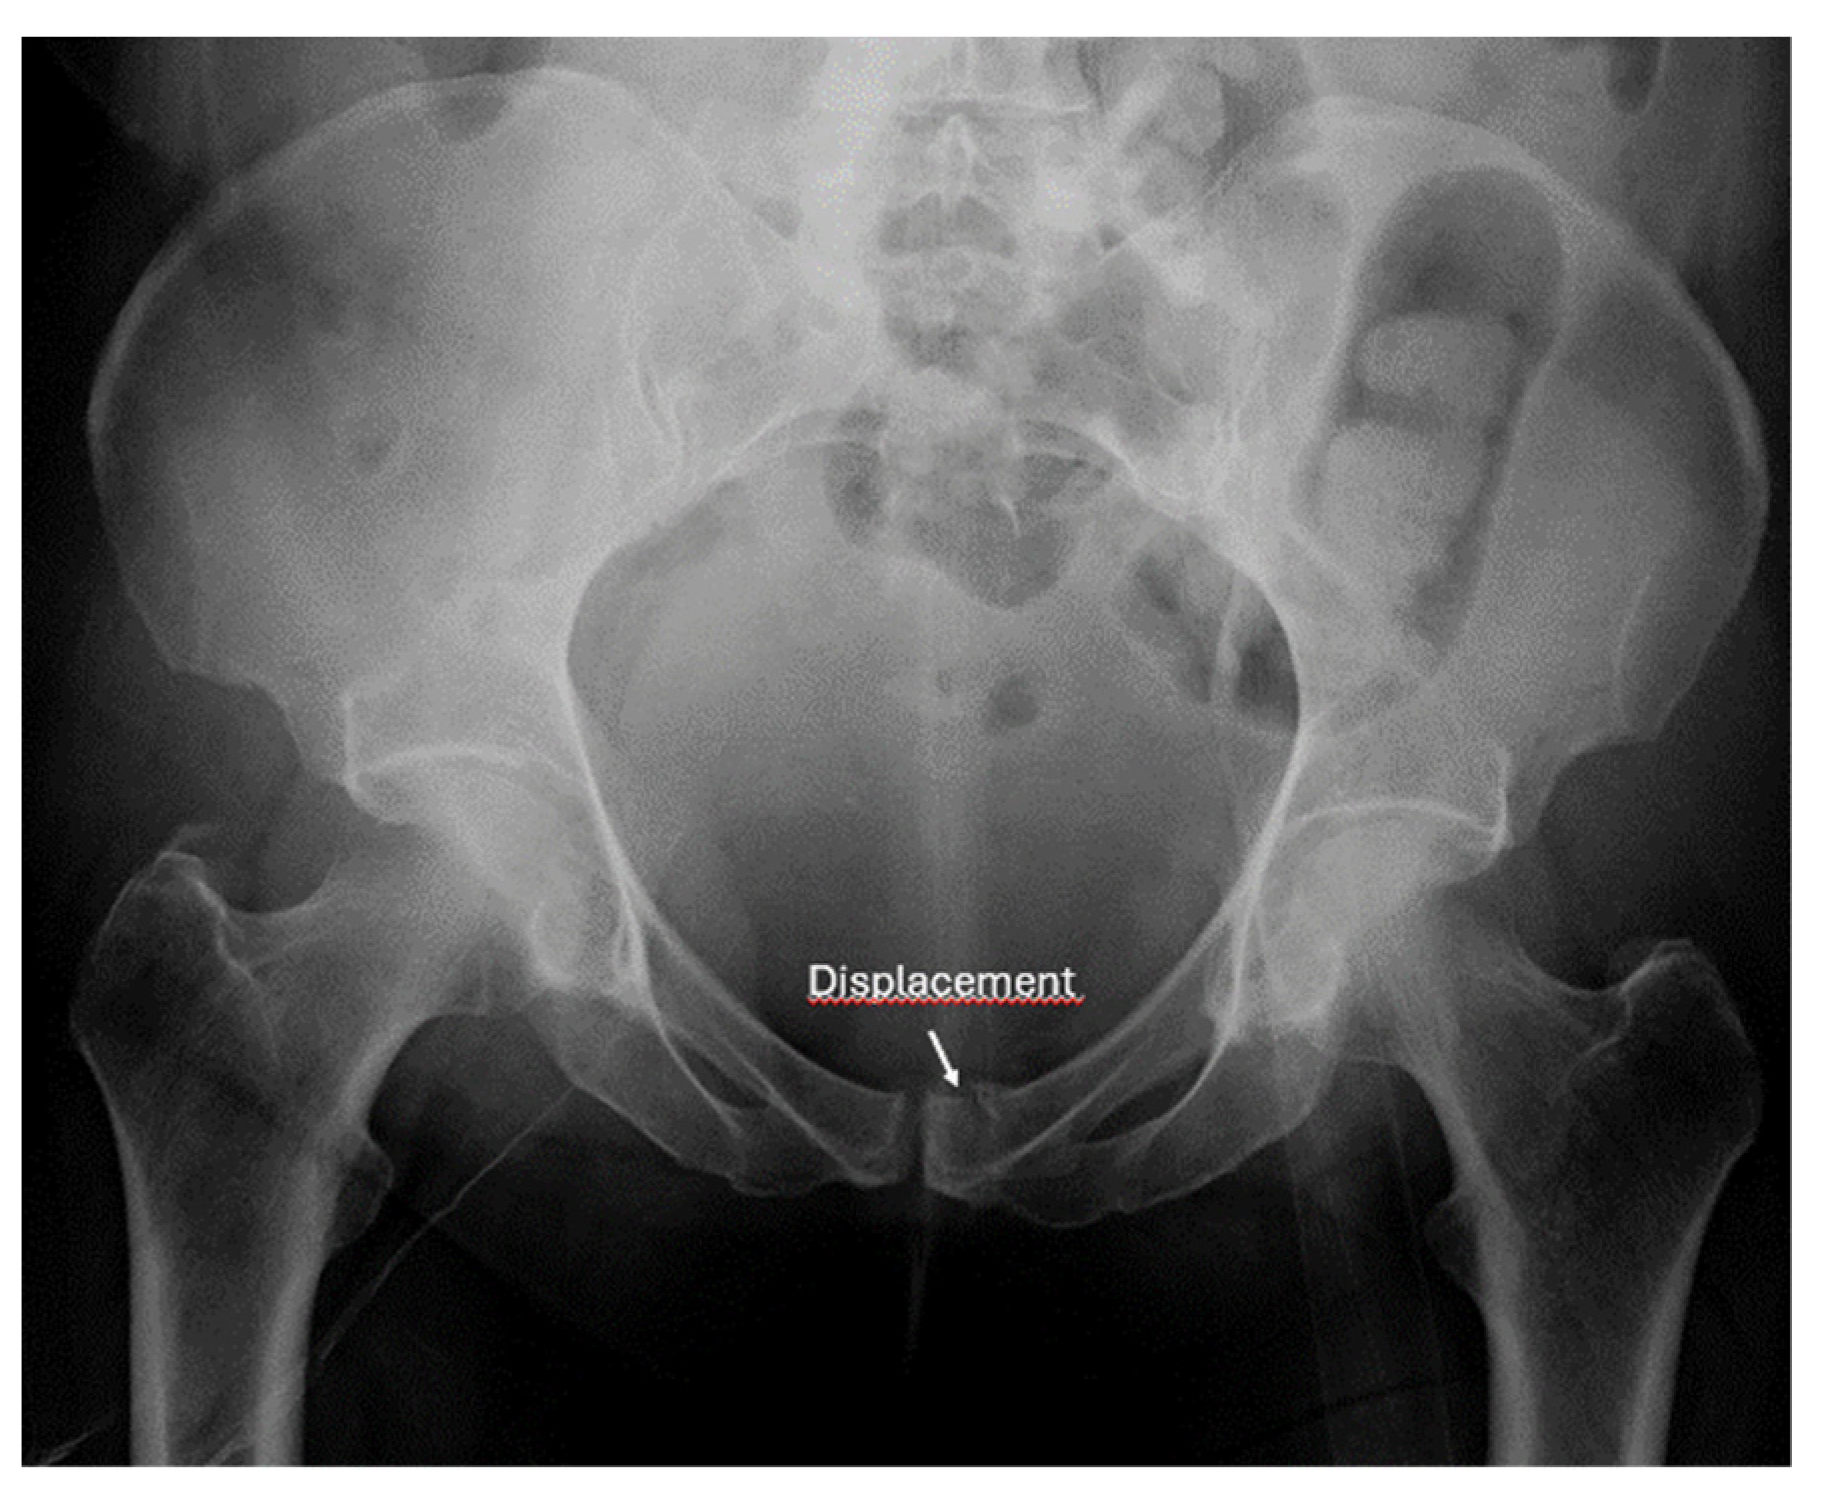

- Screening for fractures and hematoma during the primary survey in Advanced Trauma Life Support (ATLS), particularly in polytrauma patients, ultrasound enables rapid identification of fractures that are associated with life-threatening hemorrhage (e.g., pelvic or femoral fractures).

- Detection of instability signs in pelvic and spinal fractures: this is an emerging application where ultrasound can be used to assess dynamic instability or progressive displacement of fractures.

- Recommendation 4: The E-FAST protocol, indicated for severely injured patients in shock, should be expanded to include fracture screening of long tubular bones and open-book fractures when the torso scan is negative for free fluid. This could identify hidden injuries and bleeding.

- Screening for instability in pelvic and spine fractures

- Ianniello, S.; Conte, P.; Di Serafino, M.; Miele, V.; Trinci, M.; Vallone, G.; Galluzzo, M. Diagnostic accuracy of pubic symphysis ultrasound in the detection of un-stable pelvis in polytrauma patients during e-FAST: The value of FAST-PLUS protocol. A preliminary experience. J. Ultrasound 2021, 24, 423–428. [Google Scholar] [CrossRef]

- Zhang, B.-F.; Lei, J.-L.; Zhang, H.; Wang, P.-F.; Wang, H.; Cong, Y.-X.; Huang, H.; Zhuang, Y. Use of ultrasonography for evaluation of stability of lateral compression type 1 (LC-1) pelvic fractures to assist determination of treatment strategy. J. Orthop. Surg. Res. 2019, 14, 7. [Google Scholar] [CrossRef]

- Zhang, B.-F.; Zhang, H.; Wang, P.-F.; Wang, H.; Lei, J.-L.; Fu, Y.-H.; Cong, Y.-X.; Huang, H.; Huo, X.-M.; Zhuang, Y.; et al. The role of ultrasonography in examination of the stability of Tile-B2 pelvic fractures: 7 case reports and a literature review. Med. (Baltim.) 2017, 96, e8100. [Google Scholar] [CrossRef]